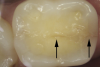

Fig 10. Stained asymptomatic enamel marginal ridge crack (arrows) of a maxillary right first molar extending to the existing restoration (mesio-occlusal view).

Figure 10

Whenever asymptomatic enamel cracks extend into dentin and cannot be eliminated by minimally invasive fissurotomy without causing additional damage to the tooth and underlying structures, protection is recommended to minimize their propagation (Figure 10 and Figure 11).3,14 Occlusal coverage restorations have demonstrated greater overall success in the treatment of symptomatic cracks by immobilizing the cracked segments that move on loading, with better prognosis seen when more conservative restorations are used.27,28 Although this might still be controversial, from a biomechanical perspective these principles can conceptually apply to the treatment of asymptomatic dentin cracks. Occlusal coverage restorations have been recommended to protect asymptomatic teeth with existing dentin cracks from further cracking (Figure 12).2,3,9,29